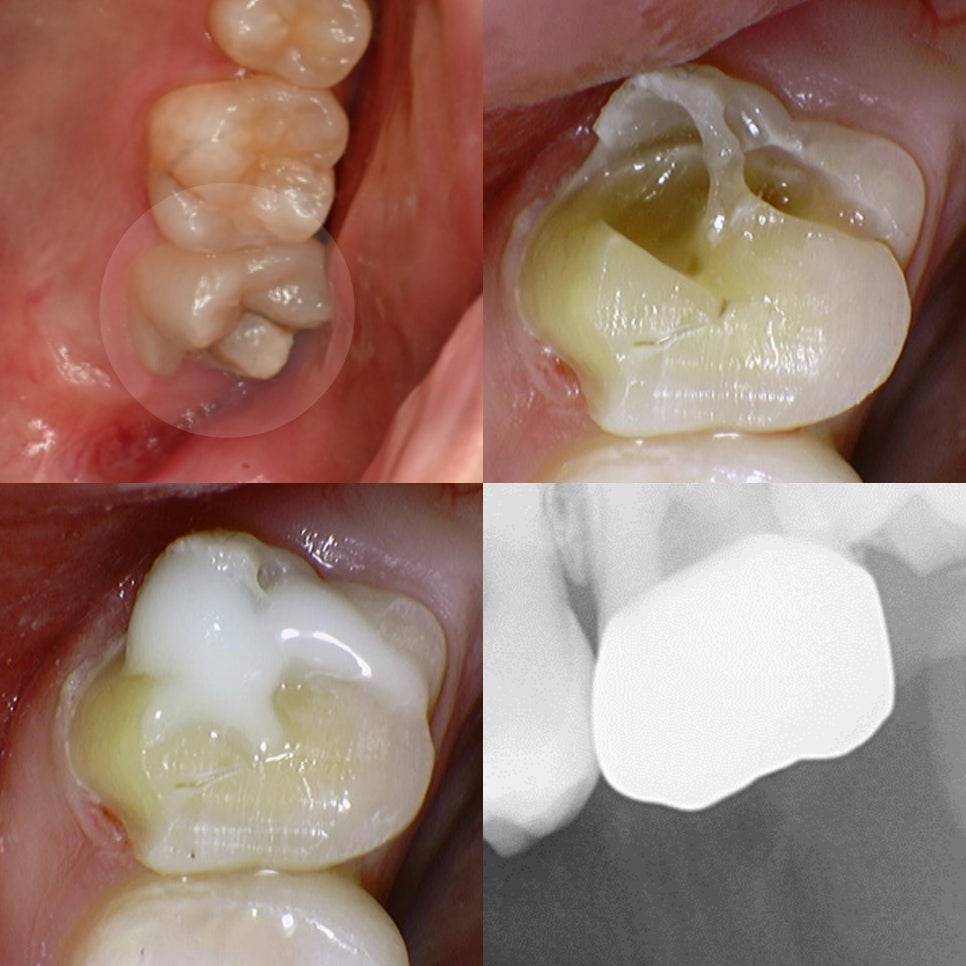

우식이 가장 깊은 경우

신경치료를 진행하게 됩니다.

겉으로는 미세한 충치처럼 보여도

치아 내부를 들여다보면

안은 훨씬 범위가 넓게 썩어 있는 것을

확인할 수 있게 됩니다.

우식 부위를 삭제하면서 근관을

찾고 내부를 확장과 괴사 조직 제거를

통해 깨끗하게 만듭니다.

이때 중요한 것이 감염 조직을

남기지 않는 것입니다.

또, 약해진 치질을 보존하기 위해

포스트(Post)를 사용하기도 합니다.

*포스트는 근관 내부에 심어 치아를

지지해 주는 기둥과 같은 역할을 합니다.

이후 빠른 시일 내로 크라운을 씌워 정상적인

식사가 가능하도록 합니다.